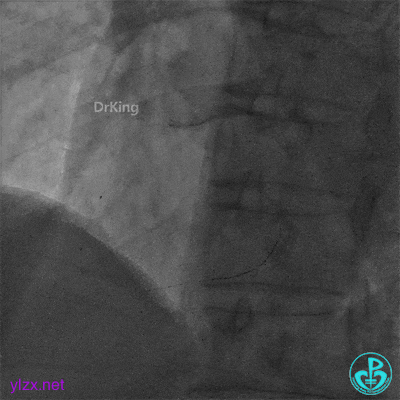

急诊冠脉造影

粗大前降支中段严重狭窄,血流3级。

粗大右冠脉中段严重狭窄,血流3级。